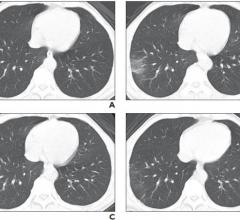

April 6, 2020 — Children and teenagers with COVID-19 showed distinctive clinical and computed tomography (CT) findings ...

April 2, 2020 — Updated computed tomography (CT) scoring criteria that considers lobe involvement, as well as changes in ...